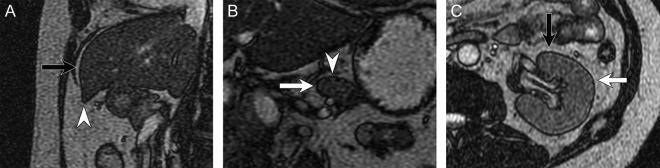

This study assessed abdominal organ motion induced by gastroduodenal motilities in volunteers during fasting and postprandial states, using cine magnetic resonance imaging (cine-MRI). Thirty-five volunteers underwent cine-MRI while holding their breath in the fasting and postprandial states. Gastric motility was quantified by the amplitude and velocity of antral peristaltic waves. Duodenal motility was evaluated as the change of duodenal diameter. Abdominal organ motion was measured in the liver, pancreas and kidneys. Motion was quantified by calculating maximal organ displacement in the left-right, antero-posterior and caudal-cranial directions. Median antral amplitude and velocity in the fasting and postprandial states were 7.7 and 15.1 mm (P < 0.01), and 1.3 and 2.5 mm/s (P < 0.01), respectively. Duodenal motility did not change. Median displacement for all organs ranged from 0.9 to 2.9 mm in the fasting state and from 1.0 to 2.9 mm in the postprandial state. Significant increases in abdominal organ displacement in the postprandial state were observed in the right lobe of the liver, pancreatic head and both kidneys. Differences in the median displacement of these organs between the two states were all <1 mm. Although the motion of several abdominal organs increased in the postprandial state, the difference between the two states was quite small. Thus, our study suggests that treatment planning and irradiation need not include strict management of gastric conditions, nor the addition of excess margins to compensate for differences in the intra-fractional abdominal organ motion under different gastric motilities in the fasting and postprandial states.

本研究采用电影磁共振成像(cine-MRI)评估空腹和餐后志愿者胃十二指肠运动引起的腹部器官运动。35 名志愿者在空腹和餐后状态下屏气进行 cine-MRI。通过测量胃窦蠕动的振幅和速度来量化胃动力。通过十二指肠直径的变化来评估十二指肠动力。测量肝脏、胰腺和肾脏的腹部器官运动。通过计算左右、前后和头尾方向的最大器官位移来量化运动。空腹和餐后状态下胃窦的平均振幅和速度分别为 7.7mm 和 15.1mm(P<0.01)和 1.3mm/s 和 2.5mm/s(P<0.01)。十二指肠动力没有变化。所有器官在空腹状态下的平均位移为 0.9 至 2.9mm,在餐后状态下为 1.0 至 2.9mm。在餐后状态下,肝脏右叶、胰头和双肾的腹部器官位移显著增加。两种状态下这些器官的平均位移差异均<1mm。尽管在餐后状态下几个腹部器官的运动增加,但两种状态之间的差异相当小。因此,我们的研究表明,在计划治疗和进行放疗时,不必严格管理胃的情况,也不必增加额外的边界来补偿空腹和餐后不同胃动力状态下的分次内腹部器官运动差异。